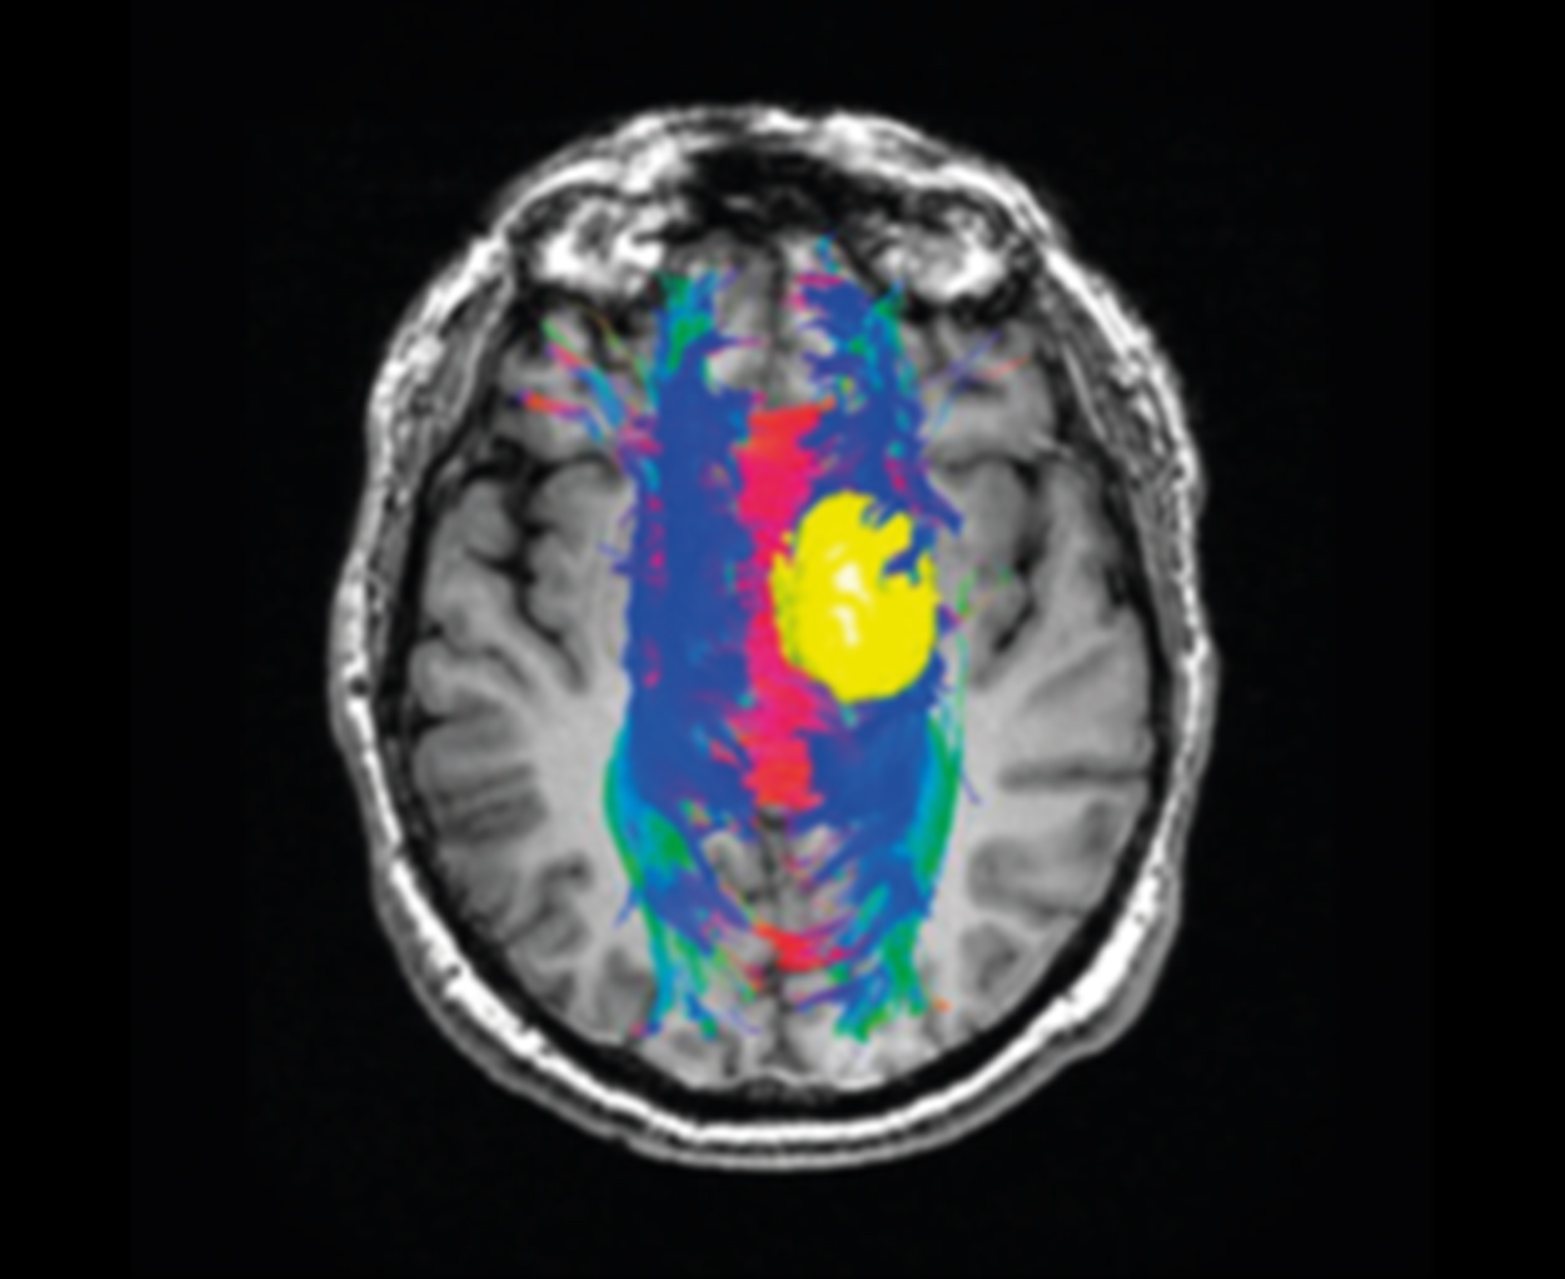

- Предоперационное планирование с трактографией и отображением волокон на обычных картах

Отслеживание волокна и объединение с обычными картами